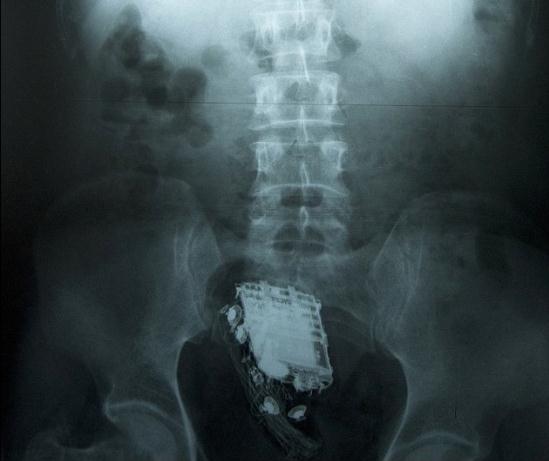

這名58歲的男子因偷盜罪被判處10年監(jiān)禁,目前正在斯里蘭卡首都科倫坡的韋利卡達(dá)監(jiān)獄服刑。為了能把手機(jī)順利取出,獄警后來(lái)把他送進(jìn)了醫(yī)院。X射線掃描顯示,手機(jī)被深深地塞進(jìn)了直腸里。